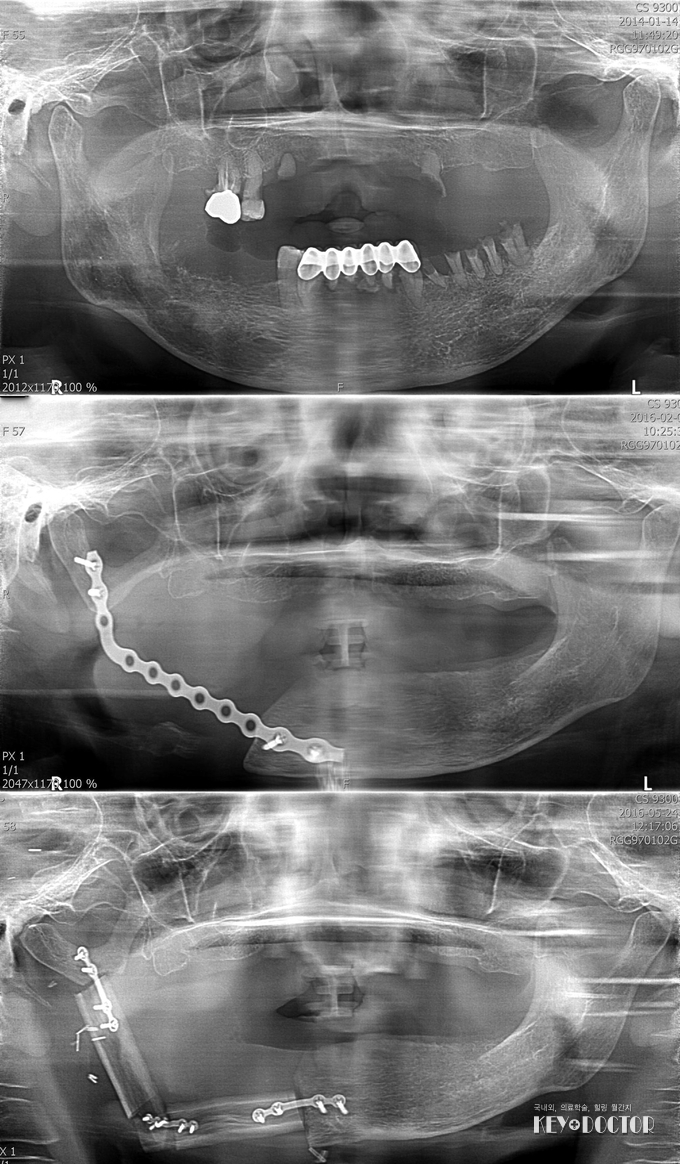

가톨릭대학교 부천성모병원 구강악안면외과 표성운 교수와 성형외과 이중호 교수에게 턱재건수술을 받고 새로운 삶을 살게 된 주인공은 경기도 시흥에 거주하는 A(58세, 여성)씨로, A씨는 2014년 입안에 생긴 염증이 낫지 않고 피가 나는 등의 증상으로 동네 병원을 찾았다가 표성운 교수에게 의뢰되어 구강암으로 진단, 수술을 받은 바 있는 환자다.

당시에도 가족이 없고 가정 형편이 안 좋아 선뜻 수술을 결정하지 못 하던 A씨를 표 교수가 적극적으로 설득하고 사회사업팀으로 의뢰하여 A씨의 목숨을 살릴 수 있었다. 하지만 구강암으로 인해 위턱 치아는 물론 아래턱 절반이 상실되어 고형(固形)의 음식섭취가 불가능하고 안면 기형으로 대인 기피증이 생기는 등 재건수술이 불가피한 상황이 되었고, 연이은 수술에 대한 두려움과 거액의 의료비를 마련할 방법이 없다는 이유로 A씨는 구강암 제거수술 이후 2년여간 병원을 찾지 않았다. 그러다 올 2월 사회로 복귀하고 싶다는 결심이 선 A씨가 표 교수를 찾았고, 표 교수가 다시 사회사업팀에 도움을 요청하면서 한마음한몸운동본부로부터 900만원에 달하는 의료비를 지원받게 됨에 따라 지난 5월 9일 표 교수와 성형외과 이중호 교수의 공동 집도로 1차 턱 재건수술을 받게 된 것이다.

턱 재건수술은 다른 부위에서 뼈와 혈관을 채취해서 턱뼈를 만드는 고난이도수술로, 먼저 성형외과 이중호 교수가 아래턱뼈를 대신하기 위한 뼈와 혈관을 A씨의 종아리뼈에서 떼어내고 안면부의 혈관에 연결시키는 유리비골피판술을 실시한 후, 구강악안면외과 표성운 교수가 떼어낸 뼈를 절골하고 형태를 복원하는 순으로 진행됐다. 수술 시간만 12시간이 넘게 걸렸지만 수술은 성공적으로 끝났고, 수술 후 경과도 좋아 앞으로 추가 골이식과정을 거치면 임플란트 시술까지 가능해질 정도로 호전됐다.

A씨가 새로운 삶을 살 수 있기까지 가장 큰 역할을 한 표성운 교수는 "우리 병원 사회사업팀의 적극적인 지원과 성형외과 이중호 교수와 협진할 수 있었기에 고난이도의 수술을 성공적으로 마칠 수 있었다”며 “앞으로 임플란트 등 할 일이 많이 남았지만 잘 진행되리라 기대되며, A씨가 건강하고 자신 있는 삶을 살 수 있게 되어 기쁘다”고 말했다.